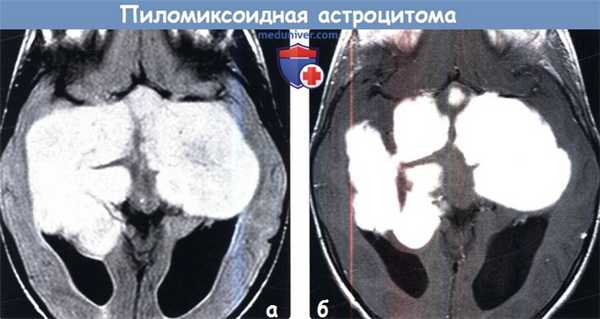

(а) На рисунке коронального среза изображена пиломиксоидная астроцитома (ПмА). Отмечается массивное объемное образование в виде буквы «Н», локализованное преимущественно в области гипоталамуса/хиазмы зрительных нервов и распространяющееся в обе височные доли. Опухоль относительно хорошо отграничена от окружающих тканей, перифокальный отек выражен слабо/отсутствует. Характерен блестящий миксоидный матрикс. Геморрагический компонента встречается - в 20% пиломиксоидная астроцитома (ПмА), он не характерен для классической пилоцитарной астроцитомы (ПА).

(б) МРТ, Т2-ВИ, корональный срез: у младенца с крупными размерами головы определяются выраженное расширение боковых желудочков и дольчатое гиперинтенсивное супраселлярное объемное образование. (а) MPT, FLAIR, аксиальный срез: у того же пациента определяется крупное объемное образование, полностью заполняющее супраселлярную цистерну, приподнимающее и «инкапсулирующее» обе средние мозговые артерии. Объемное образование имеет умеренно гиперинтенсивный по отношению к коре сигнал.

(б) МРТ, постконтрастное Т1-ВИ, SPGR, аксиальный срез: у того же пациента определяется интенсивное и достаточно однородное контрастирование объемного образования. Форма в виде буквы «Н» и преимущественная локализация в области супраселлярной цистерны являются классическими признаками пиломиксоидной астроцитомы, которая была подтверждена в ходе операции.